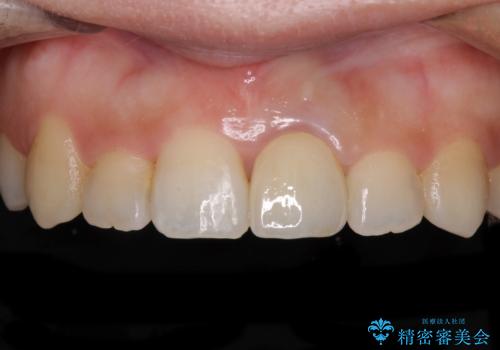

前歯のクロスバイトと変色した歯 ワイヤー矯正とセラミック治療

- 前歯のクロスバイトと神経を取り除いた後に変色してしまった前歯を気にして来院された患者様です。

ワイヤー矯正により矯正治療を行った後に、前歯の補綴治療を行うこととしました。

変色してしまった前歯は、反対側の歯と比べて歯肉が覆い被さっていたため、骨整形を含めた歯周外科処置を行い、歯肉ラインを整えることとしました。